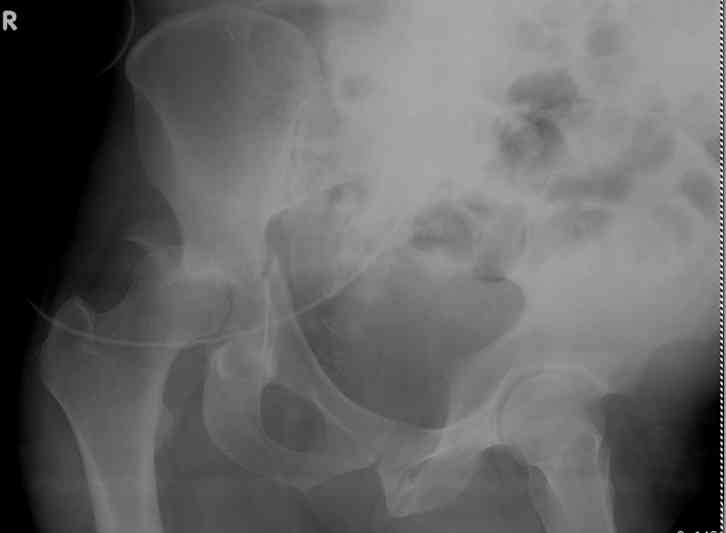

-AC Screw

-PC Screw

For Alex... here are some cannulated and 7mm screws for you... notice the fracture malreduction as indicated by the head subluxation on both views...this was a percutaneous technique without open reduction... I don¹t like it but there it is... the fixation technique is not at fault, because there was no open reduction of the fracture... but let¹s not get in to all that.